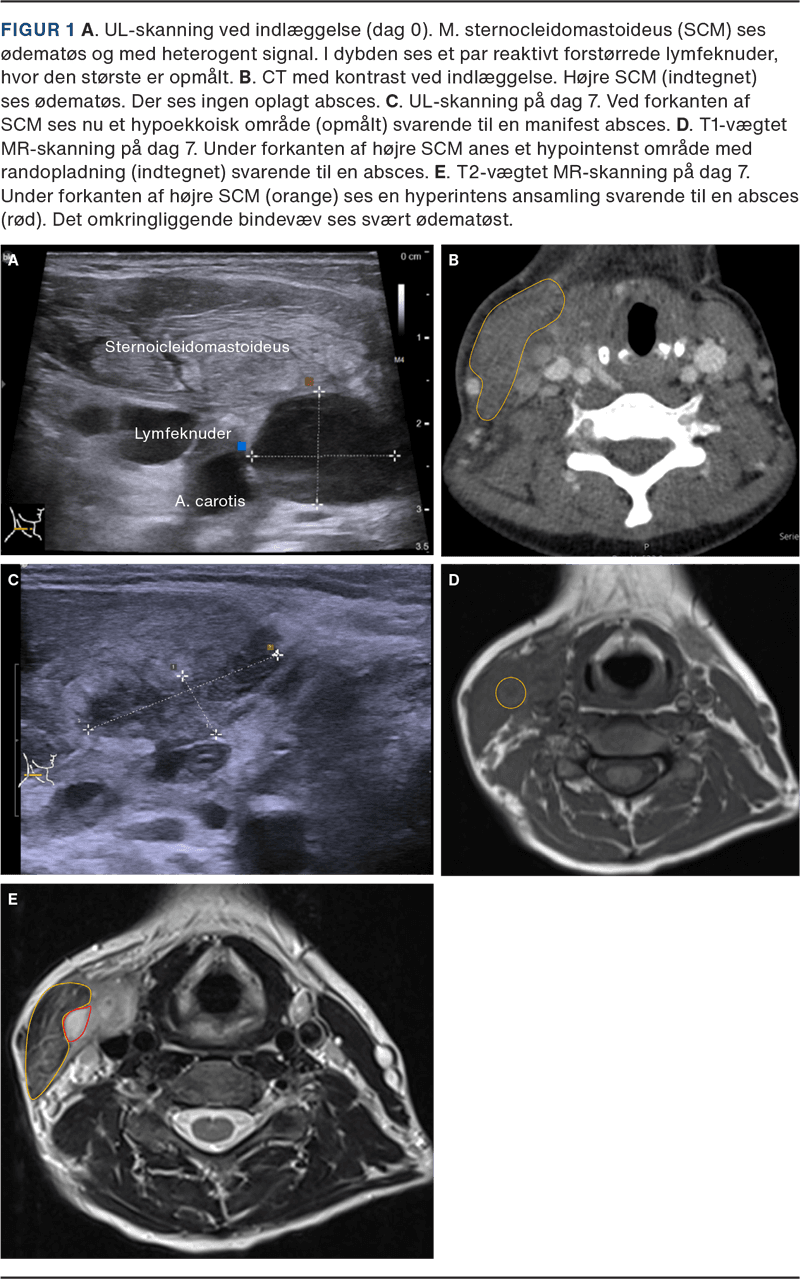

Ved øre-næse-hals-vurdering var tonsillerne højrøde med hvide belægninger, og forholdene i pharynx var symmetriske. På højre side af halsen fandtes en hård, øm hævelse langs forløbet af m. sternocleidomastoideus (SCM). Den overliggende hud var uden rødme. En UL-skanning af halsen viste flegmonøse forandringer i højre SCM og lymfadenitis i højre level 2-4 (Figur 1 A). Temperaturen var 39,1 °C, leukocytniveauet var 24,4 mia./l, og CRP-niveauet var 48 mg/l.

En CT med kontrast af halsen viste udtalt ødem af højre SCM og de omkringliggende bløddele, men ingen absces (Figur 1 B).

Patienten blev derfor på dag 7 undersøgt i kræftpakkeforløb. En finnålsaspiration af en ultrasonisk suspekt lymfeknude var med fund af akut inflammation uden malignitetssuspicio, og UL- og MR-skanning viste nu absces ved forkanten af højre SCM (Figur 1 C, D og E). Patienten blev derfor opereret med åbning og oprensning af en 3 × 4 cm stor absceskavitet. Hun blev udskrevet i velbefindende to dage senere med en uges empirisk penicillin til peroral indgift.